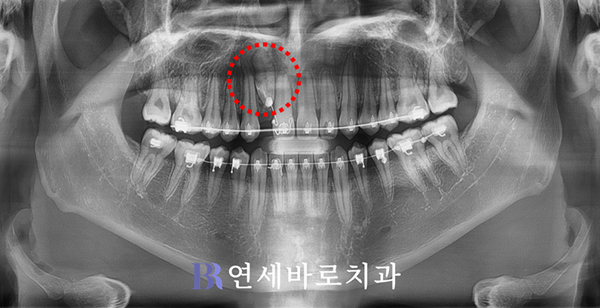

그래서 이렇게 앞니가 조금씩

내려오는 모습을 보였습니다.

본인도 중간 엑스레이를 보고

치아교정이 잘 되어간다면서

보람이 느껴진다고 하셨습니다.